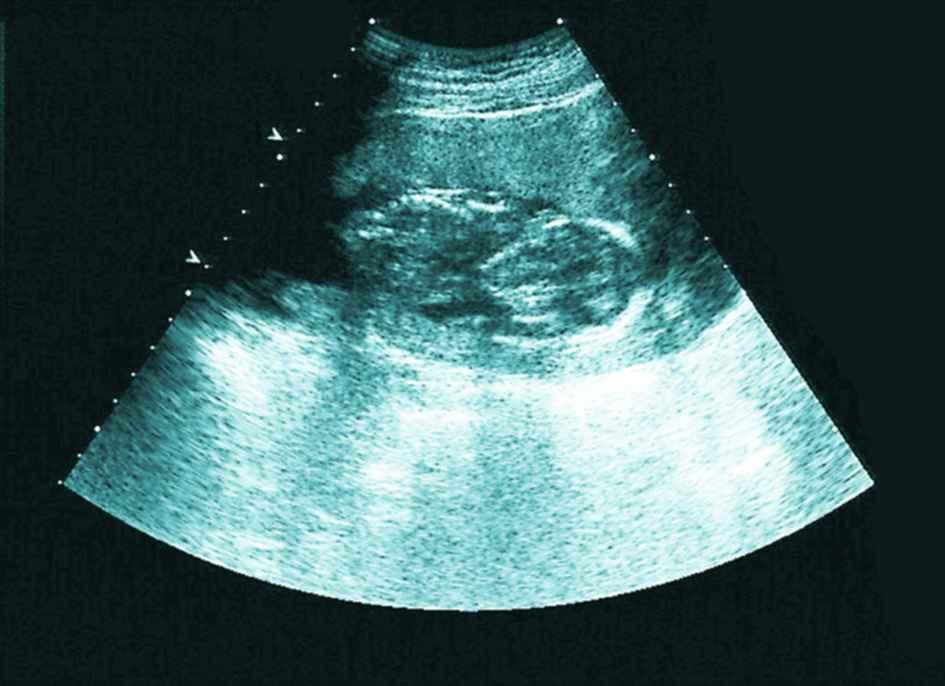

12月迟迟白带不拉丝,以为不会排卵了,到医院做了内诊和B超,又开消炎药,嘱咐我月经后通液或者造影。当时B超结果显示输卵管有优势卵泡16×14,于是回来安排功课了,没有避孕,后来几次避孕。

然而神奇的是,月经日居然测到了亲妈灰,但是颜色加深比较慢,第35天医院B超验血,没检查到孕囊,当时大夫说腹部超看不到宫外,弄得我特烦,跟他顶了几句嘴,血值hcg80不太理想,74小单位的孕酮,7天后hcg700多,又过两天hcg1044,孕酮38,也就是说在第45天,孕酮下降,于是主动B超,结果显示内膜比第35天时的薄了,且回声不均匀,宫内外都没有孕囊,大夫说孕酮下降估计是胎停,因为看不到宫内所以不给保胎。

等到能看到宫内时hcg2800多,孕酮10多一点,被宣布胎停。

孕早期,hcg数值不好,也看不到孕囊,那也不用急躁,关注看B超单,如果内膜不均匀应该是宫内孕,我在网上查阅过有姐妹这么说的,这也是我判断我不是宫外的依据。